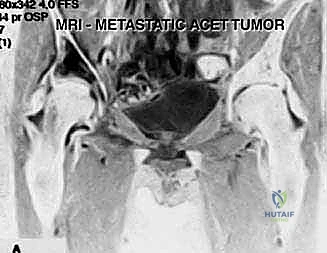

3. Magnetic Resonance Imaging (MRI): MRI is crucial for assessing soft tissue involvement and, most importantly, the integrity of the acetabular cartilage. Metastatic bone disease typically respects cartilage, so we expect to see a preserved cartilage border. This confirms our ability to perform an extra-articular resection without violating the joint.

FIG 2 • A. T2-weighted MRI scan showing the preserved cartilage border of the right hip joint.